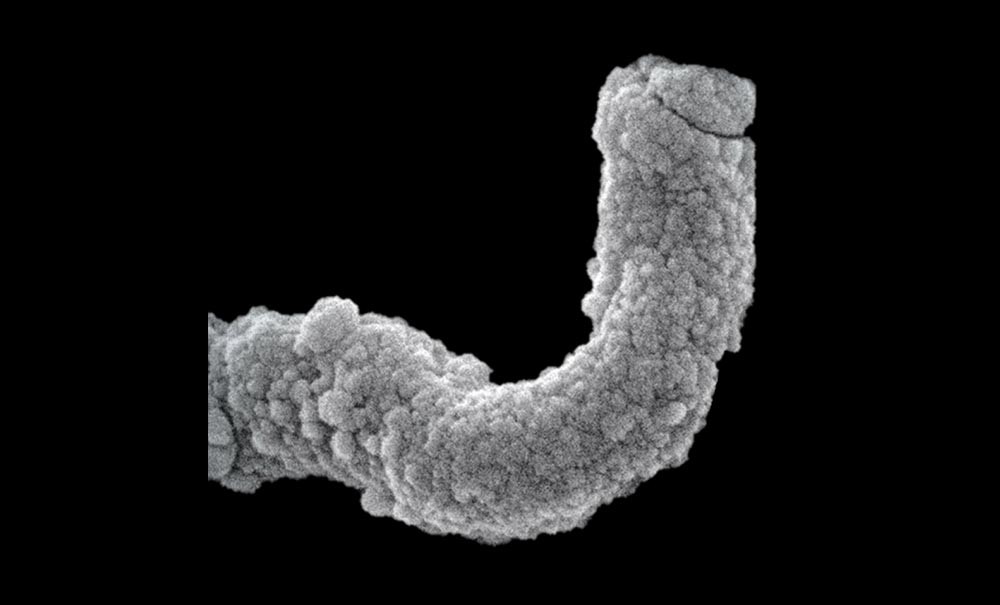

P. gingivalis est un bacille, ou coccobacille, à Gram négatif (fig. 1a), immobile, encapsulé, non sporulé, anaérobie strict. Pour l’isoler d’un biofilm dentaire, le prélèvement doit être mis en anaérobiose. Sur gélose au sang, les P. gingivalis forment des colonies, d’un diamètre variant de 1 à 2 mm (fig. 1b). Ces colonies sont lisses, brillantes et convexes. Après 4 à 8 jours de culture, elles se pigmentent progressivement en brun foncé ou noir (fig. 1c), et une hémolyse est présente (fig. 1d). La bactérie est de petite taille (0,5 à 1 µm de diamètre pour une longueur de 2 µm). Elle peut être visualisée en microscopie con- focale (fig. 2a), en microscopie électronique en transmission (fig. 2b) et en microscopie électronique à balayage (fig. 2c).